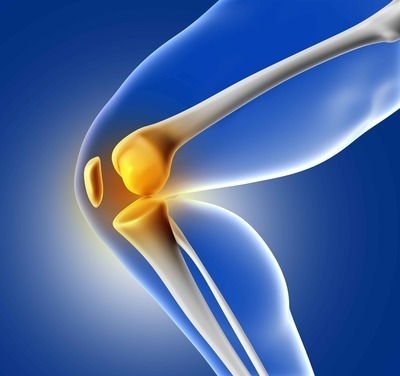

ACL Injury

Usually, a tear or strain to ACL is referred to as ACL Injury.

ACL might get torn or strained when it comes under high pressure and involves sudden changes in directions or sudden stops. These kind of situations usually occur while playing sports. Hence it is common to see ACL injury among people who play soccer, basketball, football and downhill skiing.

There is also a chance that ACL injury can happen when you come to a sudden stop while riding a bike and land on your leg in an improper way. Sometimes, ACL injury may occur during vehicular accidents.

In the case of small ACL tears, the surgeons will let it heal naturally. In the case of major ACL injury, the only treatment option is ACL Reconstruction.